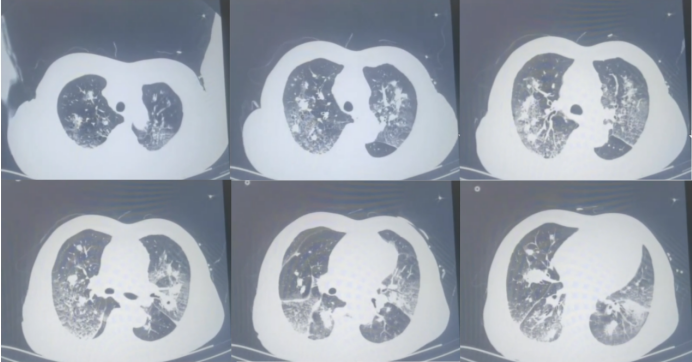

神志清楚,精神一般,桶状胸,触觉语颤减低,叩诊呈过清音,听诊双肺呼吸音粗,可闻及两肺散在湿啰音,双下肢不肿。胸部CT:下肺出现空洞样病变似有新月征表现(图13)

图片

13  患者入院时胸部CT(2023-04-21)

4月26日患者病情进一步加重,胸闷气喘非常明显。胸部CT:原有空洞样病变进一步加重,右肺和左肺也出现新的空洞样病变(图14)

14  患者入院前胸部CT(2023-04-26)